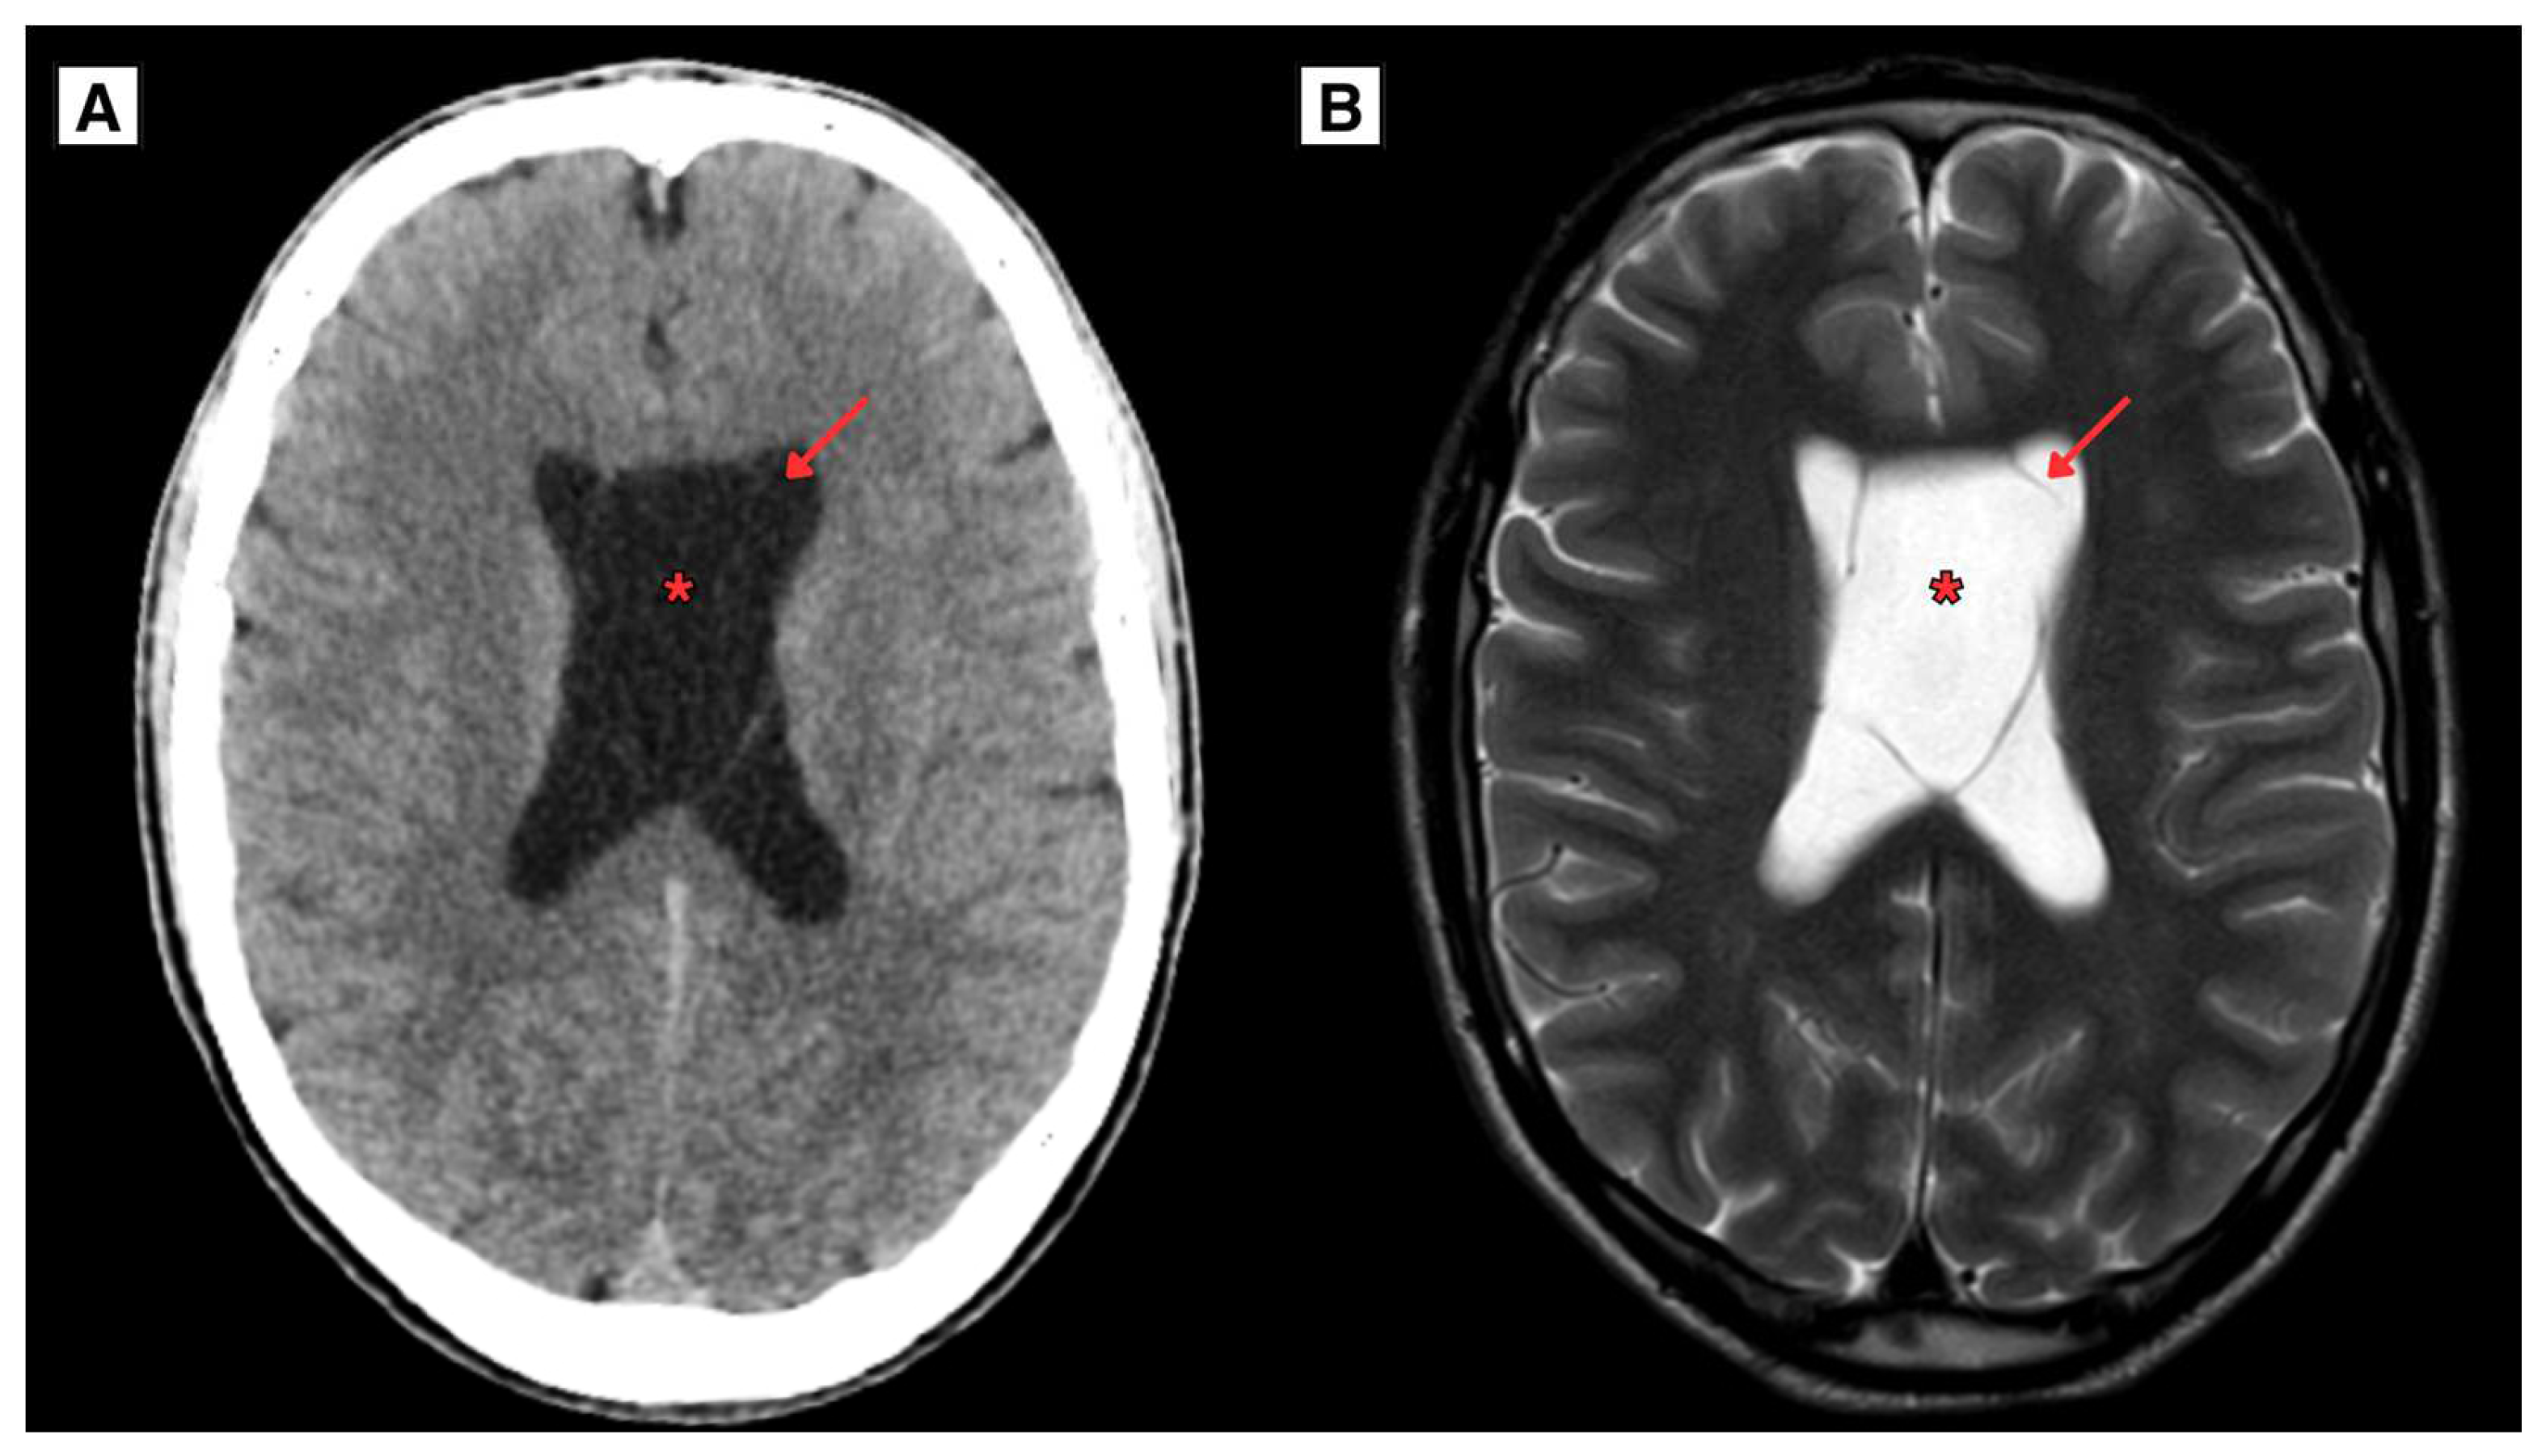

2.1. Retrospective imaging Review

2.2. A Novel Anatomical Pattern in CSP Cyst Imaging